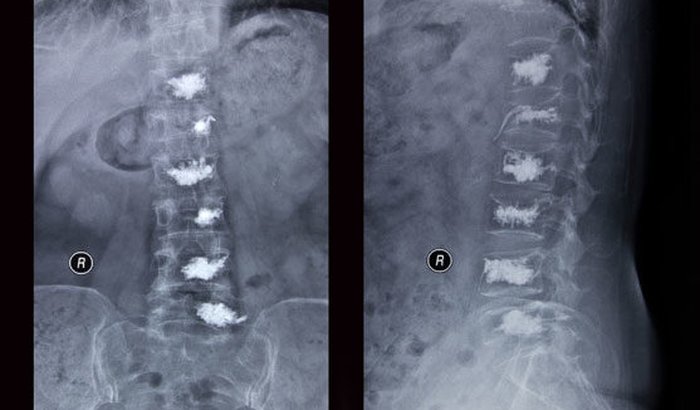

As contribuições que agora peço são para a realização de um procedimento médico em minha mãe, chamado Cifoplastia. Ela está com 5 fraturas na coluna, e esse é o procedimento para aliviar a dor e permiti-la a ter autonomia novamente, voltar a andar e se independente e super ativa como sempre foi. Caso não seja mais possível a cifoplastia, será necessário colocar pinos em toda a coluna, um procedimento mais invasivo e caro, cerca de R$70.000,00.

O valor inicial informado para a realização da cifoplastia foi de R$27.500,00 em três vezes. Contabilizamos os valores que tínhamos foram empenhados em exames pré-operatórios, e estes ultrapassaram os R$6.000,00.

A CIFOPLASTIA não é paga pelo SUS e estamos tentando evitar que minha mãe fica muito tempo acamada, pois isso traria outras complicações para sua saúde. Estamos pedindo a Deus que apenas uma cifoplastia mais o tratamento para a osteoporose seja suficiente para lhe reestabelecer a saúde. Mas há a possibilidade de ter que se colocar os parafusos ( não sei como chama esse procedimentos dos parafusos). Então a minha meta é conseguir os valor de R$30.000,00 que é o valor da cifoplastia, dos exames que ainda faltam, da continuidade do tratamento, e das mudanças que deverão ser feitas na casa dela, como barras de apoio, alargamento das portas.